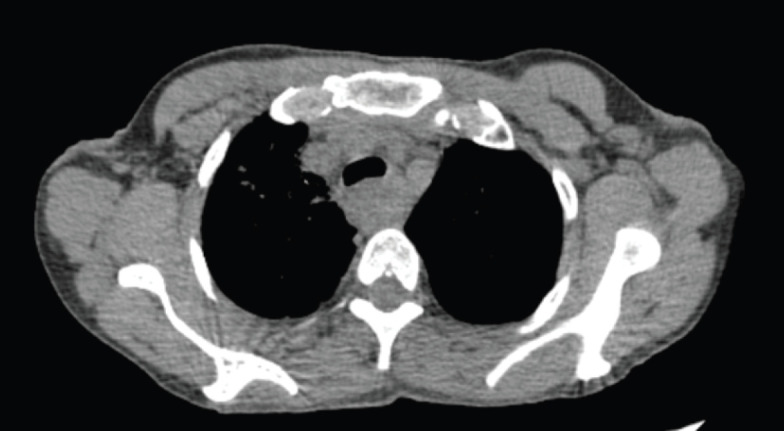

Abstract Image